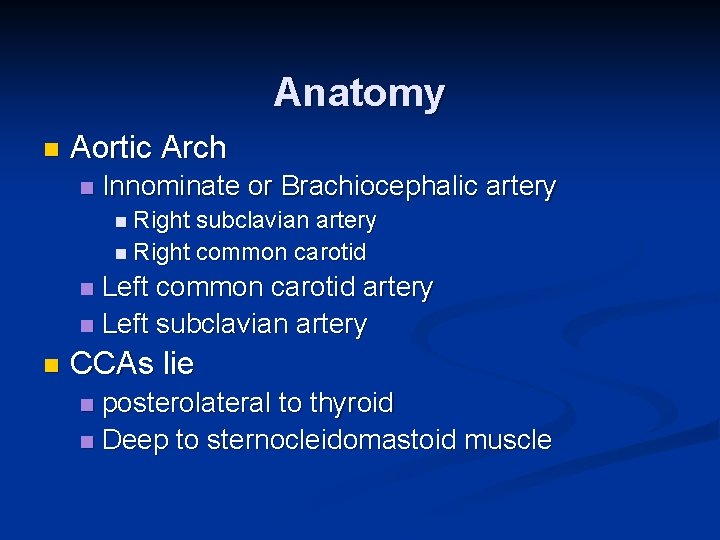

Anatomy n Aortic Arch n Innominate or Brachiocephalic artery n Right subclavian artery n Right common carotid Left common carotid artery n Left subclavian artery n n CCAs lie posterolateral to thyroid n Deep to sternocleidomastoid muscle n

Anatomy Right CCA originates from innominate artery n Left CCA originates from aortic arch n CCAs divide into ECA and ICA n ICA has no branching vessels in the neck; may have slight dilation just past its origin; supplies face and head; lies posterior in the neck n ECA has branching vessels; usually smaller than ICA n n Vertebral Arteries – lie between transverse